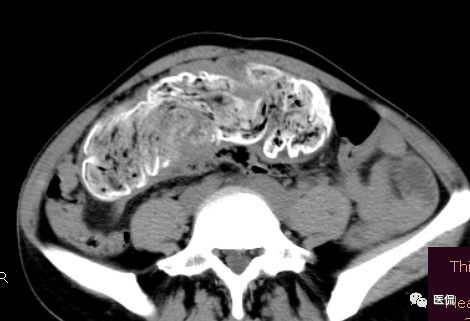

女 40岁 ,10年前做个剖腹产术。之后到现在一直感觉肚子疼,去很多医院做检查 诊断肠结核,经过反复抗结核治疗。病人10年瘦了几十斤。

腹腔内残留的纱布在人体内引起渗出或液化坏死并纤维包裹形成异物性脓肿(纱布瘤)。纱布瘤的影像特点:圆形或卵圆形肿块,较大,有完整包膜,薄壁,较少的情况下为厚壁,边界较完整,增强后薄膜可以持续强化。不同时期的纱布瘤可以有不同表现:早期(10个月或半年内)多表现为蜂窝状;2~5年内一般表现为囊性飘带状;10~20年之后则为实性软组织密度,包膜钙化呈钙化网状结构。手术过程中残留在人体内的医用纱布所形成的肿瘤样病变。

纱布团遗留腹腔后,首先由大网膜及邻近肠管将其紧密粘连并包裹,自肠管与纱布团粘连处开始逐渐向周围扩展产生纤维结缔组织包膜直至完全包住纱布团,该包膜血管丰富,充血明显,随时间延长逐渐向纱布团网眼内生长,使包膜逐渐增厚。机体还通过在包膜内产生大量异物巨细胞来围歼异物纱线,使包膜内侧形成脓肿。当包膜完全形成后,肠管与纱布团的粘连变的疏松,此时纱布团具有了一定的活动度。